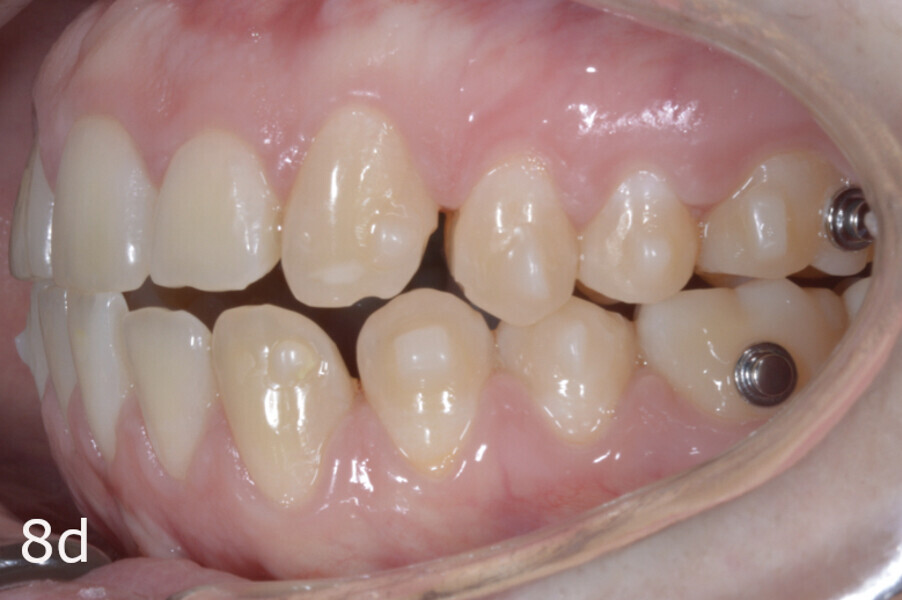

The treatment objectives included closing the anterior open bite, achieving a bilateral Angle Class I relationship and a proper overjet and overbite, correcting the midline discrepancies, and achieving a profile harmonisation. The treatment plan consisted of orthodontic camouflage treatment with asymmetric distalisation in three of the four quadrants using Invisalign aligners (Align Technology) and third molar extraction. The Invisalign Comprehensive package was chosen, and 63 pairs of aligners were used (Figs. 7–10). Each aligner was worn for 20 hours a day for one week each. The use of Class III elastics on both sides was indicated. Afterwards, ten refinement aligners were needed to improve the interdigitation on the right side (Figs. 11 & 12).

Although Class III elastics tend to extrude the maxillary molars and generate clockwise mandibular rotation, aligners allow us to prevent these complications, since we have better control over tooth movement, enabling us to counteract unwanted dental movements. In this case, an intrusion of the posterior teeth was planned, which would generate anticlockwise rotation of the mandible in an anticlockwise direction. This vertical control led to the closure of the anterior open bite and the reduction of the lower facial height, thereby improving the facial profile.

The total treatment time was 15 months. An Angle Class I relationship was established along with adequate anterior and canine guidance, establishing a functional occlusion. This not only ensures optimal masticatory function but also protects the teeth and the temporomandibular joint from excessive force. Maxillary and mandibular fixed retention were installed at the end of the treatment (Figs. 13–19).